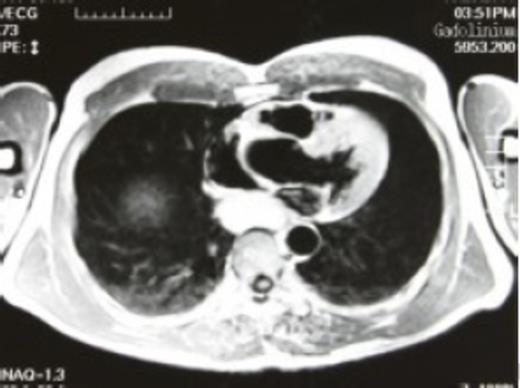

A 52-year-old man was referred due to an abnormal shadow on routine chest X-ray. His medical history included above-the-knee amputation of the left leg due to a traffic accident. He reported mild dysphagia when ingesting solid food. Physical findings were unremarkable. Computerized axial tomography (CAT) scan showed a posterior mediastinal mass compressing the oesophagus, and magnetic resonance imaging (MRI) revealed high signal intensities on both T1 and T2 weighted images suggestive of bronchogenic cyst (Fig. 1).

T1 preoperative magnetic resonance imaging - high intensity signal lesion was found in the posterior mediastinum, suggestive of a bronchogenic cyst